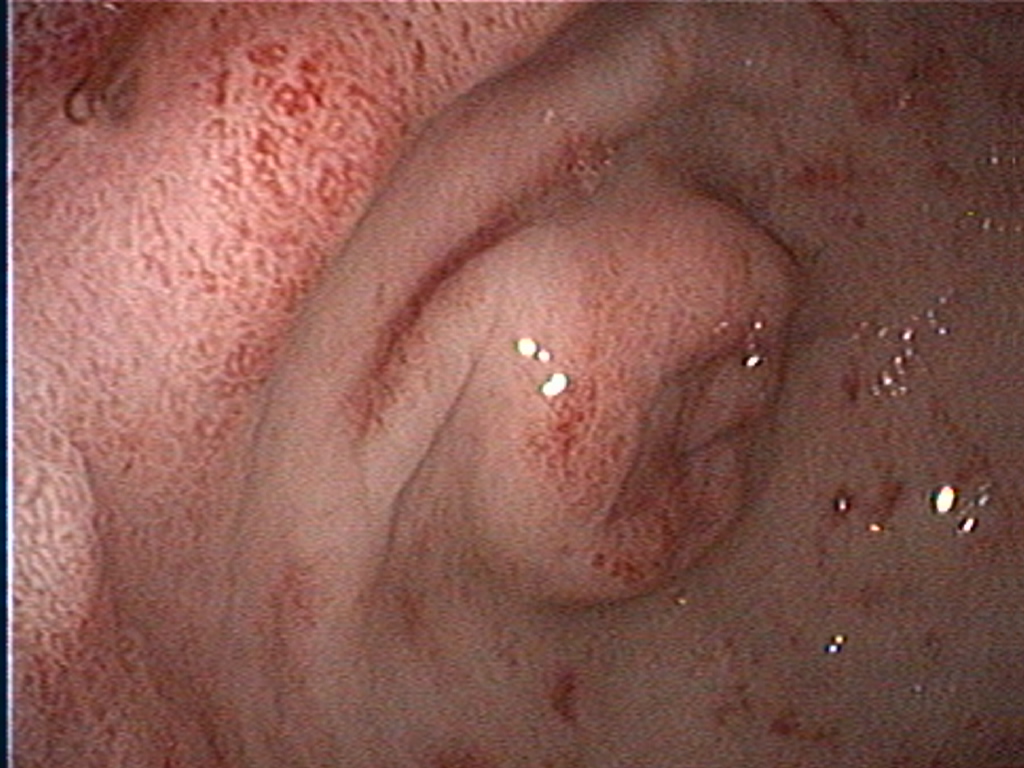

Intestinal small cell lymphoma (SCL) in cats is the most frequent digestive tract neoplasia and histology consists of small, well-differentiated lymphocytes with low mitotic rates (Paulin et al, 2018). More than 90% of intestinal SCL are of T-cell origin and are currently referred as LGITL. In practice, differentiating between lymphoplasmacytic enteritis (LPE) and LGITL remains challenging. A recent study revealed some clinical and ultrasonographic variables that can guide clinicians (Freiche et al, 2021), but ultimately, intestinal biopsies are required to achieve a definitive diagnosis.

Biopsies can be obtained via endoscopy or exploratory laparotomy. Historically, the latter was considered superior to differentiate between LPE and LGITL, however, less invasive endoscopic biopsies with ancillary test can be sufficient in some cases. The main limitation to endoscopic biopsies is the localisation of LGITL, since 64% of cases have infiltration of the jejunum only, which cannot be reached endoscopically (Freiche et al, 2021 b).